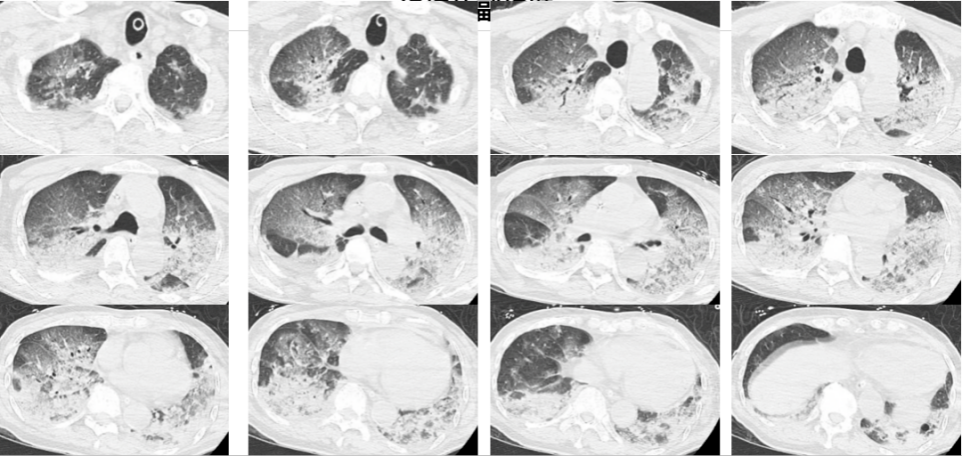

2024年12月,浙江杭州,酷爱蒸桑拿的韩爷爷(化名)于午饭后前往洗浴中心。不料刚进去没多久,整个人就昏了过去并口吐白沫,周围人帮忙拨打了120,将他送入医院。入院时,韩爷爷意识不清,血压、心率下降,医生随即为他安排头颅、胸部CT和肺血管CTA检查,结果显示,老人的双肺出现大面积白色影像。经会诊,韩爷爷被确诊为热射病诱发的肺水肿。